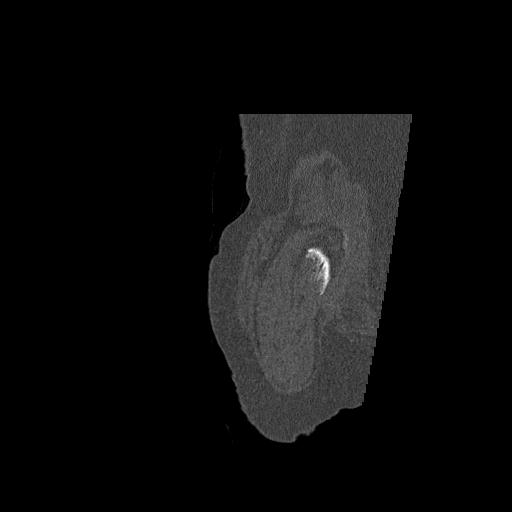

110286 2/17 股関節 2R 74歳女性 右人工骨頭

102903 股関節 2R 1/28 +股関節 2R 1/29 78歳女性 左人工骨頭

82084 1/14 1/20 股関節 2R 78歳男性 右人工骨頭

91569 3/25 両股正面とラウエン 70歳女性 人工骨頭+バンクーバー